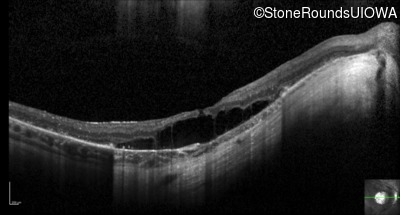

Optical Coherence Tomography - Left - 20/100

Exemplar / OCT Stack

OCT Stack